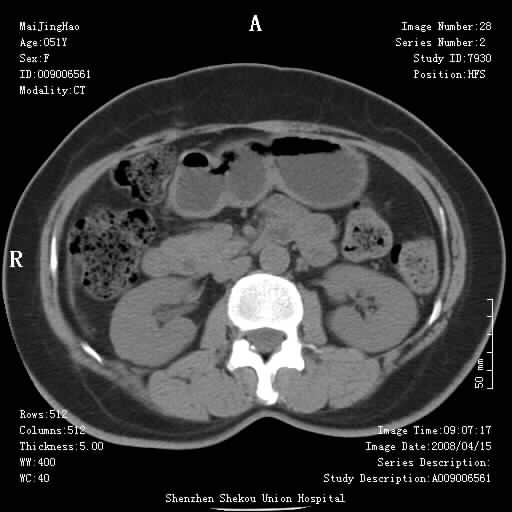

以下是引用余辉在2008-4-26 8:55:00的发言:[br]患者有结石史,此次腹痛4小时,胆总管全程扩张,应有胆总管末端梗阻,此次仍考虑胆结石症,积气不外两种原因,一种是结石下移时肠道内气体逸入,其次为产气菌感染。(倒数第三幅图像于扩张之胆总管末端似可见稍高密度影,考虑为结石影)

以下是引用听蝉观竹在2008-4-26 11:41:00的发言:[br]胆道手术分两种情况:[br]1、如果仅仅做胆囊切除手术,肝内胆管不会积气,只会出现胆总管代偿扩张,因为奥迪氏括约肌依然功能正常胆道与外界并不相通;[br][br]2、胆囊切除+胆总管空肠吻合手术(即roux-y式),则肝内胆管会出现积气,只是因为胆管与小肠相通,气体来源于小肠。这是临床十分常见的手术。[br][br]这个病例应该是胆囊切除+胆总管空肠吻合手术,是正常手术后表现,并不是胆道感染的表现。

以下是引用听蝉观竹在2008-4-27 10:10:00的发言:[br]关于胰头大小问题有几种测量方法和正常值:[br][br]1、直量法:横径<4cm;[br]2、胰头横径与相邻层面椎体横径的比值为二分之一,超过椎体横径就提示胰头增大;[br]3、正常组成年人肠系膜上动、静脉水平夹角正常值范围为4.9°~34.7°大于35°提示胰头增大。[br][br]上述方法只是一种具体的判断,是“量”的评估,更重要的是“质”的评估:一是观察边缘是否光滑,有无局部隆起,有无分叶;二是观察密度(增强,尤其在动脉期和门脉期)是否均匀。[br][br]所以对于胰头是否有异常不仅仅是是目测可以解决问题的,不要轻易就说“胰头增大”。还有一个问题就是测量胰头应该在增强ct上进行,这样可以避免将血管测量进去。[br][br]为什么啰嗦讲怎么多,因为我们实际工作中同样存在影像科医生和临床医生动不动就说胰头增大,说是胰头癌。大家看看是不是这种情况?[br][br] 我个人观点-----本病例的胰头不增大。[br][br][本贴已被 听蝉观竹 于 2008-4-27 10:12:41 修改过]